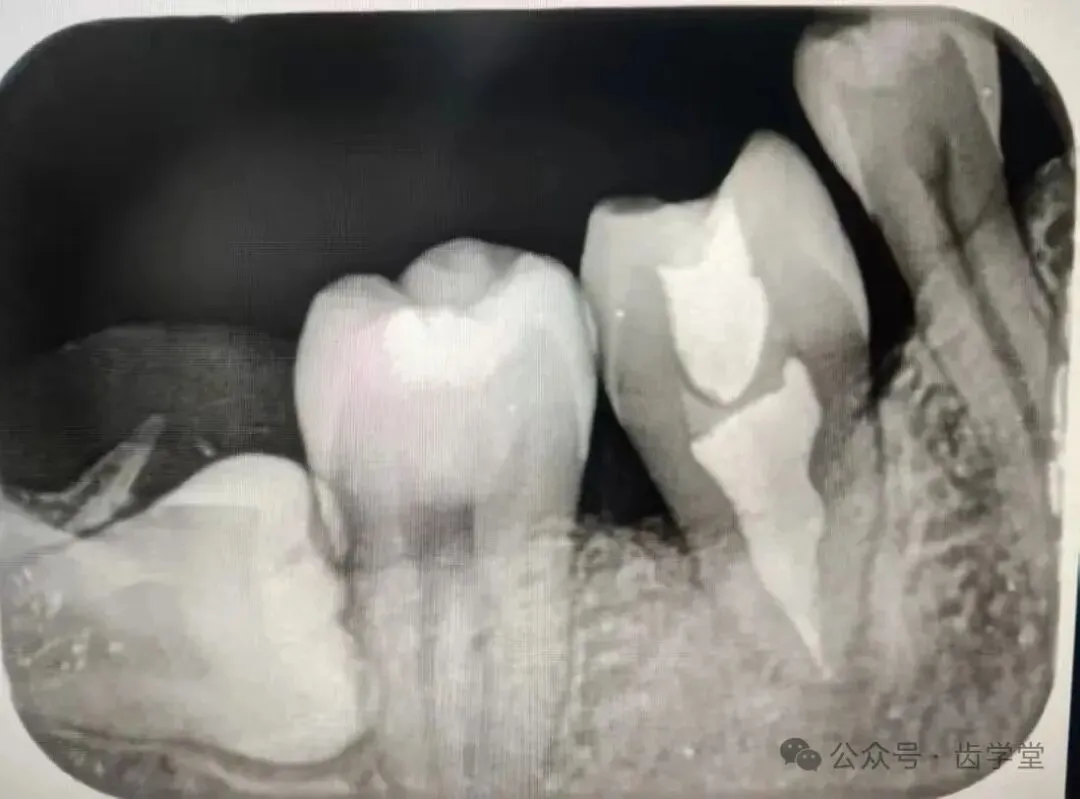

8. 自体牙移植的术前检查、评估和准备;

12.供牙微创拔除的操作要点详解;

13.受植位点不同情况移植的区别及其要点;

1.供牙八字法微创拔除技巧,牙周膜保护的方法及疑难复杂供牙术前处理方法(术前正畸类);

2.受植区患牙拔除方法,受植窝精准预备方法;